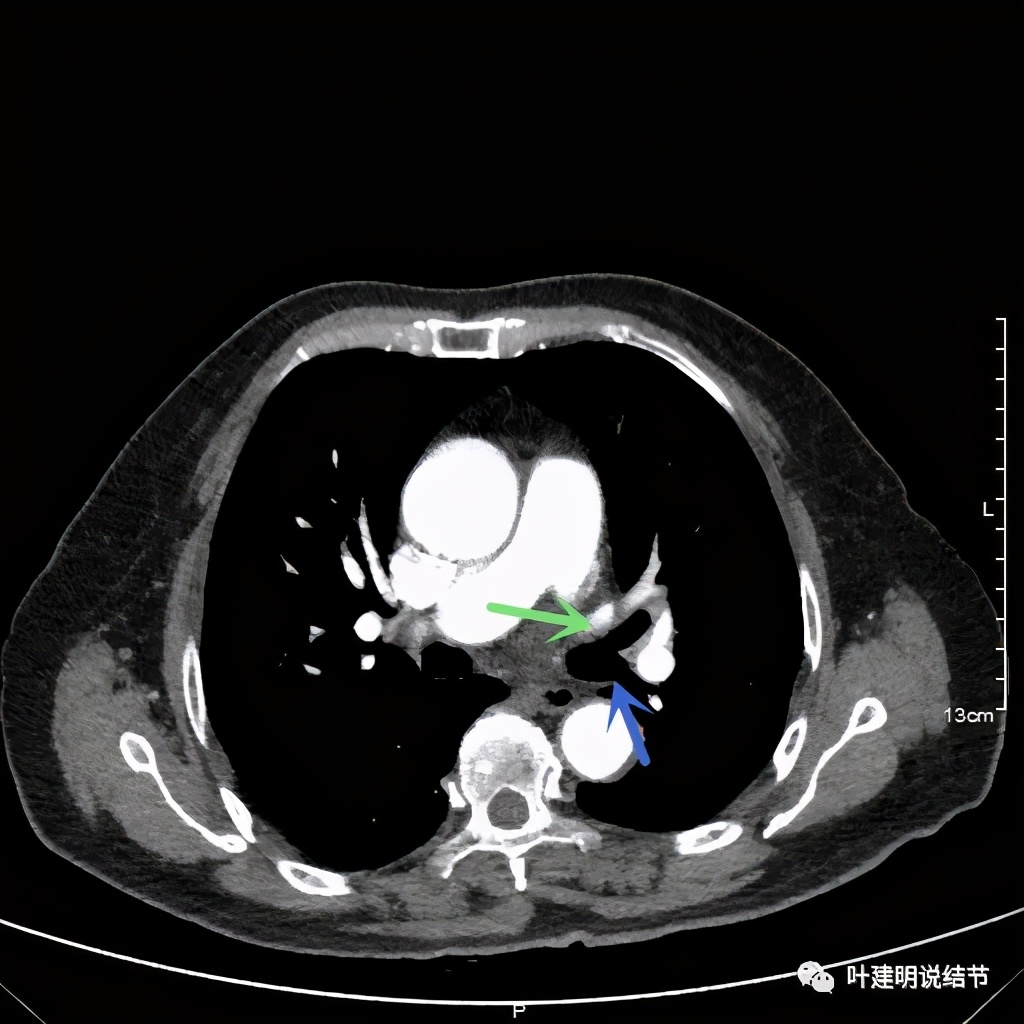

上图也示桔色箭头示左肺动脉分支处仍被软组织(原肿瘤所在)包绕,粉色箭头示肺动脉仍与肿瘤处关系密切

上图示肿瘤部位仍与肺动脉关系密切,似乎未能脱开,红色示肿瘤处

上图示原病灶处,现在不是明显的占位影像了

可见效果相当的好,如果我们把差不多同样层面的放到一起对比,更能显示化疗加免疫的惊人效果:

我样的治疗效果,显然超出了我们之前的预期,那么接下来拟选择行手术治疗,初定左上叶袖式肺叶切除加淋巴结清扫,但因为肺门区仍有软组织影,与肺动脉的关系仍密切,肿瘤与肺动脉间能否游离开来还是未知数,但至少得努力争取,鉴于患者年纪虽大,肺功能指标尚可,血气分析也基本正常,所以与患方沟通后确定行手术探查,但也也说明有万一全肺切除的可能(虽然这种可能性较小)。